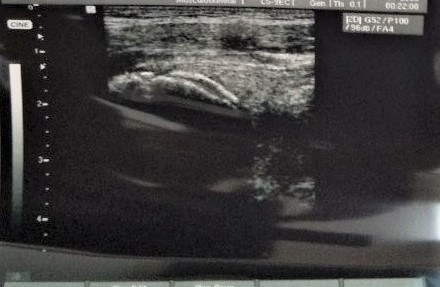

下記のエコー画像は、股関節の痛みを訴えて訪れたサッカー少年のものです。骨盤の骨なのですが、かさぶたが剥がれるような感じが、鮮明に映っております。10代のサッカーで、キック時に股関節前側が痛む場合は、この骨盤の下前腸骨棘という部分が剥離骨折を起こしてしまうことがあります⚽その場合、このような画像が見られますので、今回も第一に考えなければなりません。同じ付近での痛みは他に、上前腸骨棘の剥離骨折もあります。

当院ではエコーを用いて、ある程度の骨の状態を観察することが出来ます。すずらん当院では予約優先で施術を行っておりますので、待ち時間はさほど少ないと思われます。まずは、お気軽にご連絡ください☎